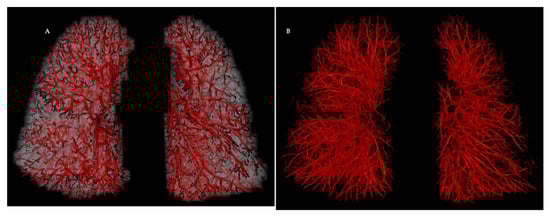

2. Pulmonary Vascular Morphometrics: Evolution from Castings to Imaging

- Clinical Applications of Morphometrics in Pulmonary Vascular Diseases